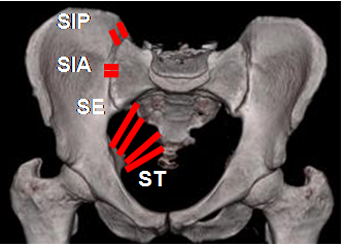

Fig 1. Ligamentos normales de articulación sacroiliaca.

Sacroiliaco posterior (SIP) y anterior (SIA), sacroespinoso (SE) y sacrotuberoso (ST).